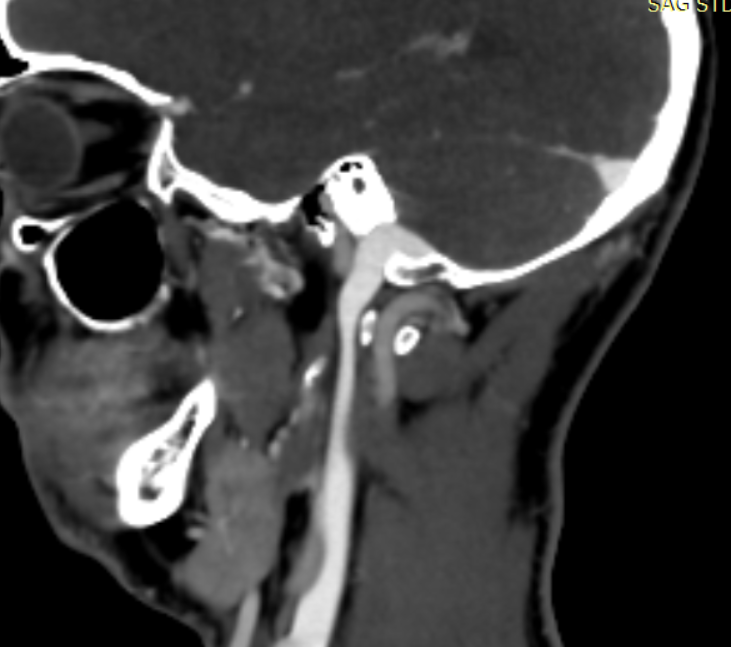

This is my story: June 2024 i had a whiplash accident where i overextended. I had some pain at the base of the skull but not that severely, had some CCI symptoms, i kept on going till the point where i got severe insomnia several weeks later. I am currently sleeping 3 hours a night structuraly with sleeping pills for 1 year now. Got tinitis especially when there is pressure on my neck (laying down). My neck is getting weaker in time and symptoms increase. I suspect that the compression of the IJV are the main cause of the sleeping problem. Or this could be because of compression of nervus vagus.

I have a cbct and CVA made wich shows elongated styloids and calcified stylohoids around 5 cm. Space left in neutral position between c1 is 3.5mm. Left IJV compression in laying position but there seems to be mainly some soft tissue compression there. So not due to compression of c1/styloid. The right is my dominant IJV.

They found a kinking carotis artery on the right at the c1 level.

Hi Rob & welcome! Looking at your CT, & obviously we’re not experts, I would estimate that your styloid & calcified ligament section is longer than 5 cm; on your left in the middle image it goes way past your C2 vertebra! We have found that the measurements from CTs are often wrong as it can be quite hard to measure accurately due to CT imaging being done in slices…

The IJVs do collapse naturally when flat, so it could be due to that, in your 3rd image it looks like the IJV is flattened higher up, so what would be right by the skull base. It could be like that naturally because of being flat for the CT, or it could be that it is being compressed where it emerges from the skull at the jugular foramen - if styloids are quite thick that is possible, & yours do look a little wide at the top… It looks like there could be something pinching the IJV between it & the styloid where you’ve marked too; we’ve had members who’ve had compression from an enlarged SCM muscle, the digastric muscle, omahyoid muscle, as well as other blood vessels & nerves… I’d guess where the compression is that the digastric muscle would be the most likely if it was a muscle, or maybe the stylohyoid muscle, although we don’t hear much about that one!

@Rob12345 - Welcome to our forum! I have nothing to add to what @Jules said, but did want to say WOW! You do have very long styloids. The “kink” in your ICA (internal carotid) isn’t really a kink more of a curve, but I can see based on the image, that it could be causing some slowed or backed up blood flow going into your brain. The IJV compression is curious as it appears to be more than the styloid causing the problem but clearly C1 seems not to be involved. I think Jules has made some logical assumptions regarding other possible compression culprits.

@Rob12345 - I can see you have bilateral IJV compression in the images you’ve posted & it’s possible the middle image in your first set of pictures is pointing to collateral veins. I’m not great at identifying collaterals, but I can say for sure your IJVs are being squashed between your styloids & C1.